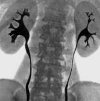

Экскреторная урография (внутривенная урография). Диагностическое исследование, которое является наиболее физиологическим методом рентгенологического исследования строения и функций мочевыделительной системы. С его помощью оценивается функциональное состояние почек, строение их тазовой почечной системы, мочеточников и в некоторых случаях состояния мочевого пузыря. Экскреторная урография позволяет обнаружить нарушения кровотока в почках, снижение их активности, наличие инородных тел (например, камня) в малом тазу или мочеточнике, аномалии анатомического строения органов мочевыделительной системы. Это исследование, выполненное с использованием контрастных соединений, может быть выполнено в случае экстренного или планового заказа - в последнем случае целесообразно провести подготовительные действия для получения более точных результатов.

Экскреторная урография

Оценивая результаты экскреторной урографии, рентгенолог или уролог учитывает ряд показателей - степень контрастности крови от почек, форму и размер комплекса таз-таз, наличие или отсутствие дефектов наполнения в сLA и мочеточники, и несколько других. При снижении функциональной активности мочевыделительной системы время поступления контраста в мочу увеличивается, что проявляется отсутствием признаков нефрографической фазы (накопление контрастного вещества в тканях почки) на 1-2 мин. после администрации.

Значительное расширение сLA, обнаруженное при экскреторной урографии, указывает на повышение давления в мочевой системе и косвенно указывает на наличие стеноза, камней, опухолей или других препятствий для оттока мочи. Последнее можно визуализировать как дефекты заполнения таза или мочеточника - именно на этом основании можно обнаружить опухоли и рентгеноконтрастные камни. Наиболее достоверные результаты получены методом экскреторной урографии с флюороскопической видеозаписью процесса контрастной изоляции.